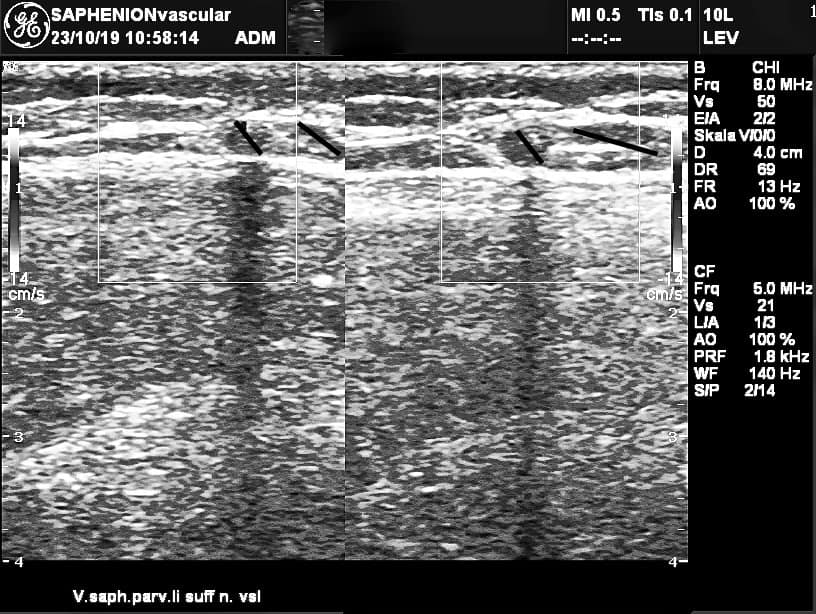

VenaSeal of junction of GSV and SSV – ultrasound control

Utzius: Ultrasound pictures